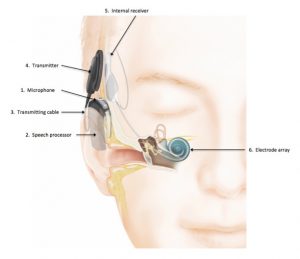

Depuis 2002, plus de 59 000 personnes ont bénéficié des prothèses neurologiques, telles les stimulateurs cardiaques, les oreilles bioniques, les valves cardiaques et les membres artificiels. Les prothèses neurologiques ont soulevé de nombreuses questions éthiques sur la sécurité du corps humain, les inclusions sociales et la sécurité.

Pour les implants cochléaires, par exemple, des risques pour la sécurité des dispositifs avaient été signalés, qui entraîneraient des lésions auriculaires. La FDA avait signalé ces risques, y compris, les lésions du nerf facial, de la méningite, des fuites de liquide céphalo-rachidien et les crises d’étourdissements ou de vertiges.

Les cyborgs avec des implants cochléaires ne peuvent pas effectuer d’autres examens médicaux et traitements de routine tels que l’imagerie par IRM et la neurostimulation. Cela risque de déloger l’implant ou de démagnétiser son aimant interne. Cependant, la FDA a approuvé certains implants pour certains types d’études IRM effectuées dans des conditions contrôlées.

Les implants cochléaires affectent également les inclusions sociales et la communication de l’individu. Parfois, les impressions sonores changent, les utilisateurs décrivent les sons comme mécaniques, techniques ou synthétiques jouant sur leurs réactions aux situations.

Les implants peuvent aussi déclencher des détecteurs de vol et d’autres systèmes de sécurité. Cela impacte le mode de vie sociale, rendant les cyborgs plus prudents avec, par exemple, les téléphones cellulaires, les émetteurs radio et même l’électricité statique qui peut endommager les implants.